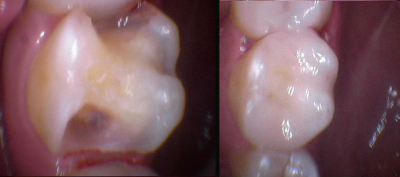

Gallery

Galeria